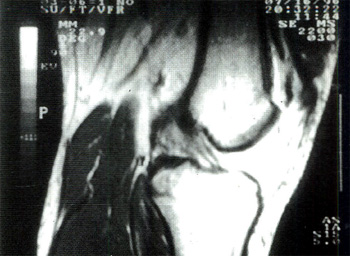

Fig. 1 Corte sagital oblicuo paralelo al LCA.

El pedido de estudio indicaba "esguince de rodilla", el mismo se realizó en todos los casos antes de la artroscopía. Empleamos un resonador superconductivo de 0,5 Tesla marca Toshiba modelo MRT 50 A con bobina cuadratica diseñada para rodilla.

Se obtuvo una secuencia rápida coronal T1 de tres cortes. Tomando como inclinación una tangente al borde inferior de los condilos femorales, obtuvimos una segunda secuencia idéntica pero en el plano axial. Sobre esas imágenes axiales, se marco el plano sagital-oblicuo, siguiendo la dirección del LCA.

Sistematicamente obtuvimos secuencias spin eco densidad protonica y T2 (plano sagital oblicuo), spin eco T1 (planos coronal y axial) y, eventualmente, T2 según lo observado, en planos coronal y/o axial.

Empleamos cortes de 5mm. y campos de exploración de 15 cm.